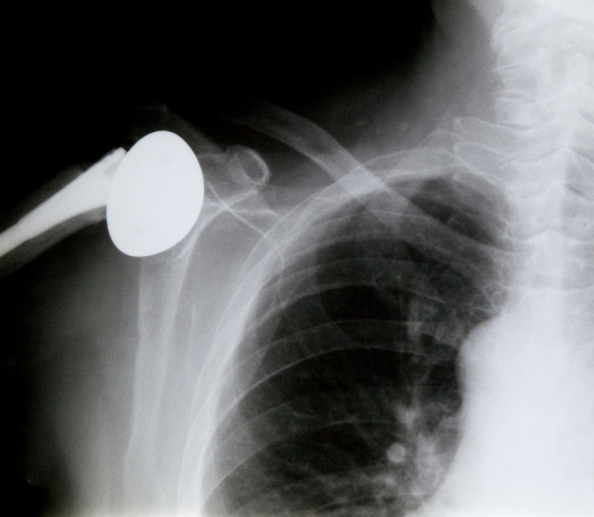

Schulterprothesen

Eine Schulterprothese ersetzt geschädigte Gelenkflächen. Die Wahl zwischen Totalendoprothese (TEP) und Teilprothese richtet sich nach der Schädigung von Schulter und Rotatorenmanschette. TEP ersetzt beide Gelenkpartner, während die Teilprothese nur den Schulterkopf erneuert. Bei fortgeschrittener Schulterarthrose (Omarthrose) verbessert der Gelenkersatz Schmerzen und Beweglichkeit.

Schulterprothesen kommen mithilfe eines chirurgischen Eingriffs zum Einsatz, wenn andere Behandlungen erfolglos waren.

Minimalinvasive Schultergelenksendoprothese

Bei fortgeschrittenem Schultergelenksverschleiß (Omarthrose), der durch verschiedene Ursachen wie Rheuma, Veranlagung oder durch einen Unfall entsteht und operativ nicht mehr behandelbar ist, kann eine minimalinvasive Schultergelenksendoprothese eingesetzt werden. Diese Prothesen helfen auch bei Oberarmkopfbrüchen oder Muskelmanschettenverlust. Die Implantatwahl richtet sich nach Sehnenfunktion, Knochenbeschaffenheit und der zugrunde liegenden Erkrankung.